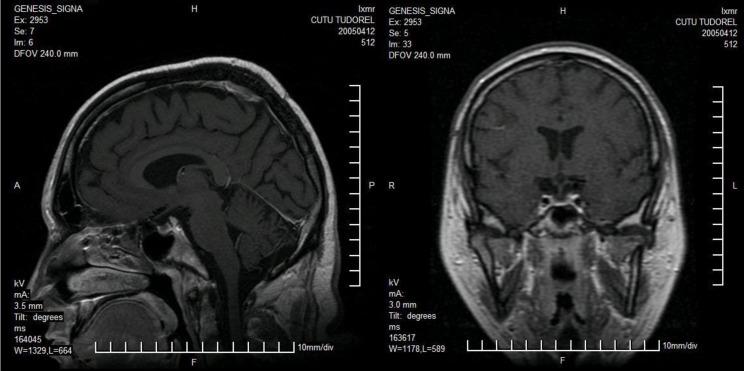

Alstrom syndrome is an extremely rare, autosomal recessive genetic disorder characterized by a group of signs and symptoms including infantile onset dilated cardiomyopathy, blindness, hearing impairment/loss, obesity, diabetes, hepatic and renal dysfunction. Since the first description of the syndrome in 1959, there have never been reported cases of Alstrom syndrome with the occurrence of the Bardet-Biedl syndrome in their relatives, this case suggesting a close genetic link between these two ciliopathies. The presence of empty sella seems to be a rare morphologic finding in Alstrom syndrome although it has been documented in few Bardet-Biedl cases.

We report a case of a 20 -year-old caucasian male with hearing and visual loss, short stature, insulin resistant diabetes, dilated cardiomyopathy, hepatic and renal dysfunction, hypertension, and alopecia. By studying his family medical records we identified two relatives with suggestive clinical findings for Bardet Biedl syndrome.

阿尔斯特伦综合征是一种极其罕见的常染色体隐性遗传病,其特征是一组体征和症状,包括婴儿期发病的扩张型心肌病、失明、听力障碍/丧失、肥胖、糖尿病、肝肾功能障碍。自1959年首次描述该综合征以来,从未有亲属发生巴德-比德尔综合征的阿尔斯特伦综合征病例报告,该病例表明这两种纤毛病之间存在密切的遗传联系。空蝶鞍的存在似乎是阿尔斯特伦综合征中一种罕见的形态学表现,尽管在少数巴德-比德尔病例中已有记录。

我们报告一例20岁的白种男性病例,该患者有听力和视力丧失、身材矮小、胰岛素抵抗性糖尿病、扩张型心肌病、肝肾功能障碍、高血压和脱发。通过研究他的家族病历,我们确定了两名有巴德-比德尔综合征提示性临床发现的亲属。